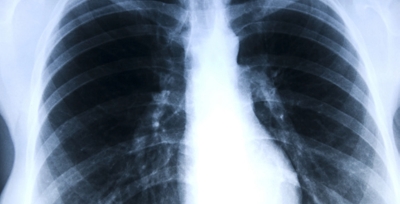

Inteligencia artificial que detecta enfermedades pulmonares antes de que sea tarde

Según la Organización Mundial de la Salud (OMS), cada año mueren 3.23 millones de personas por enfermedad pulmonar obstructiva crónica (EPOC) en el mundo, y en Colombia se estima que fallecen más de 13.800 personas, lo que equivale a 38 muertes diarias. Según estudios nacionales, entre 2.7 y 4.7 millones de adultos mayores de 40 años en Colombia padecen EPOC, pero cerca de 2 millones no han sido diagnosticados. Esta brecha se debe a la falta de tecnologías de diagnóstico y el hecho de que muchos médicos generales no priorizan solicitar las pruebas, al considerar que los síntomas son consecuencia de la vejez.